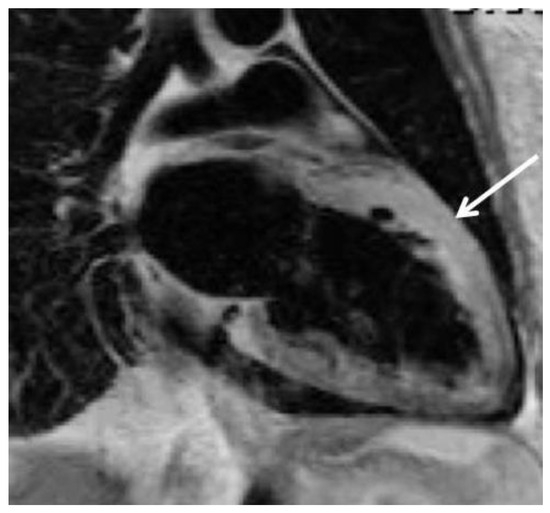

The fact that non-valvular (non-rheumatic) atrial fibrillation creates detectable thrombi in 17% of patients without oral anticoagulation and that 16% of the 17% (over 90% relatively) reside in the left atrial appendage (LAA), suggest that patients w...